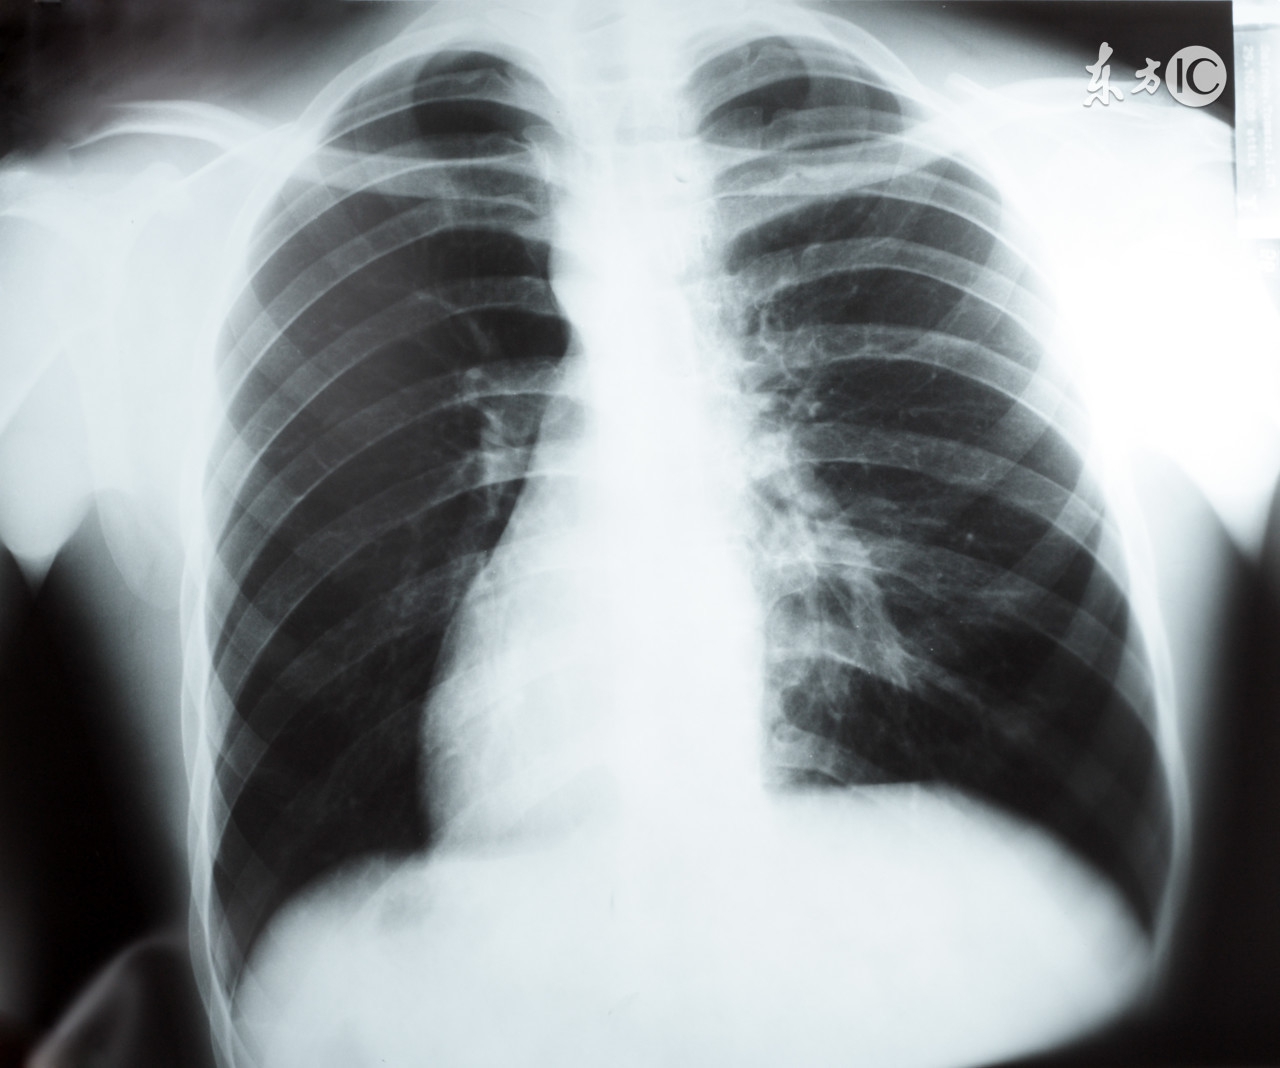

很多人会遇到这种情况:体检或因为其他疾病做检查,偶然发现肺部结节,于是问:发现肺结节怎么办? 这个要看大小、质地等综合判断,很多肺部疾病(包括良性和恶性)会表现为结节。如果发现可疑肺癌结节,应首先进行多学科评估,也就是说,胸外科医生、胸部放射学家和肺科医生等共同来确定癌症诊断的可能性以及最佳的诊断或随访策略安排。这其中的重要内容就是进行风险评估,包括患者方面的因素(年龄、吸烟史、既往肿瘤史、家族史、职业接触、其他肺部疾病情况如慢阻肺、肺纤维化等、传染性或感染性病原体接触(如真菌感染、结核病疫区)史或表明感染的高危因素或病史如免疫抑制、呼吸、传染性呼吸道症状等;影像学因素(肺结节的大小、形状、密度等、相关的肺实质异常如疤痕或可疑炎性改变、PET影像中的氟脱氧葡萄糖活性等。